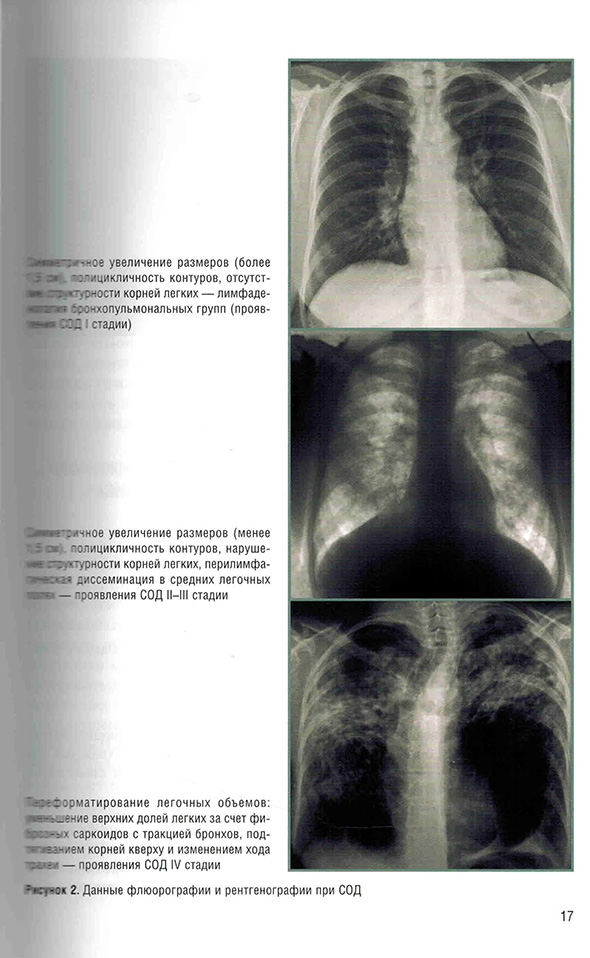

Клинико-лучевые стадии саркоидоза органов дыхания